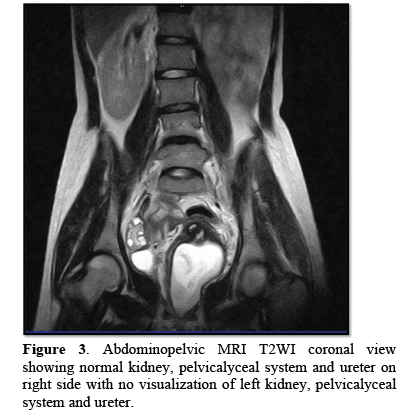

18 year’s old unmarried female was admitted in our casualty with complaints of acute abdomen. Acute onset in pain which was moderate in intensity, continuous without any relieving or aggravating factors mainly localized in the lower abdomen and associated with vomiting. Her previous menstrual cycle was 3-4/28-30 days with complaints of dysmenorrhea and LMP was two weeks back. She was stable and there was no pallor. Her pulse was 84 bpm, BP- 110/80 mmHg, RR- 20/min. On examination, there was slight tenderness and an ill-defined mass felt in left iliac fossa with rebound tenderness. On speculum examination, cervix was flushed with vagina; bulge is seen right vaginal wall. A cystic non-tender mass felt in right fornix with restricted mobility projecting in vagina on bimanual examination. So, possibility of appendicular lump or left TO mass was kept. Blood investigations were normal. Urine pregnancy test (UPT) was negative. Transabdominal ultrasonography showed septated uterus, cervix and vagina with non-visualization of left kidney. A cystic mass showing internal echoes on the left side of vagina and a septate uterus with blood in the cavity was noted. On MRI abdomen and pelvis, a complete septate uterus with haematocolpus of left hemivagina with absent left kidney and solitary right kidney showing hypertrophy was noted i.e., OHVIRA syndrome (Figures 1-3).